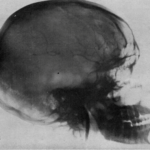

angio